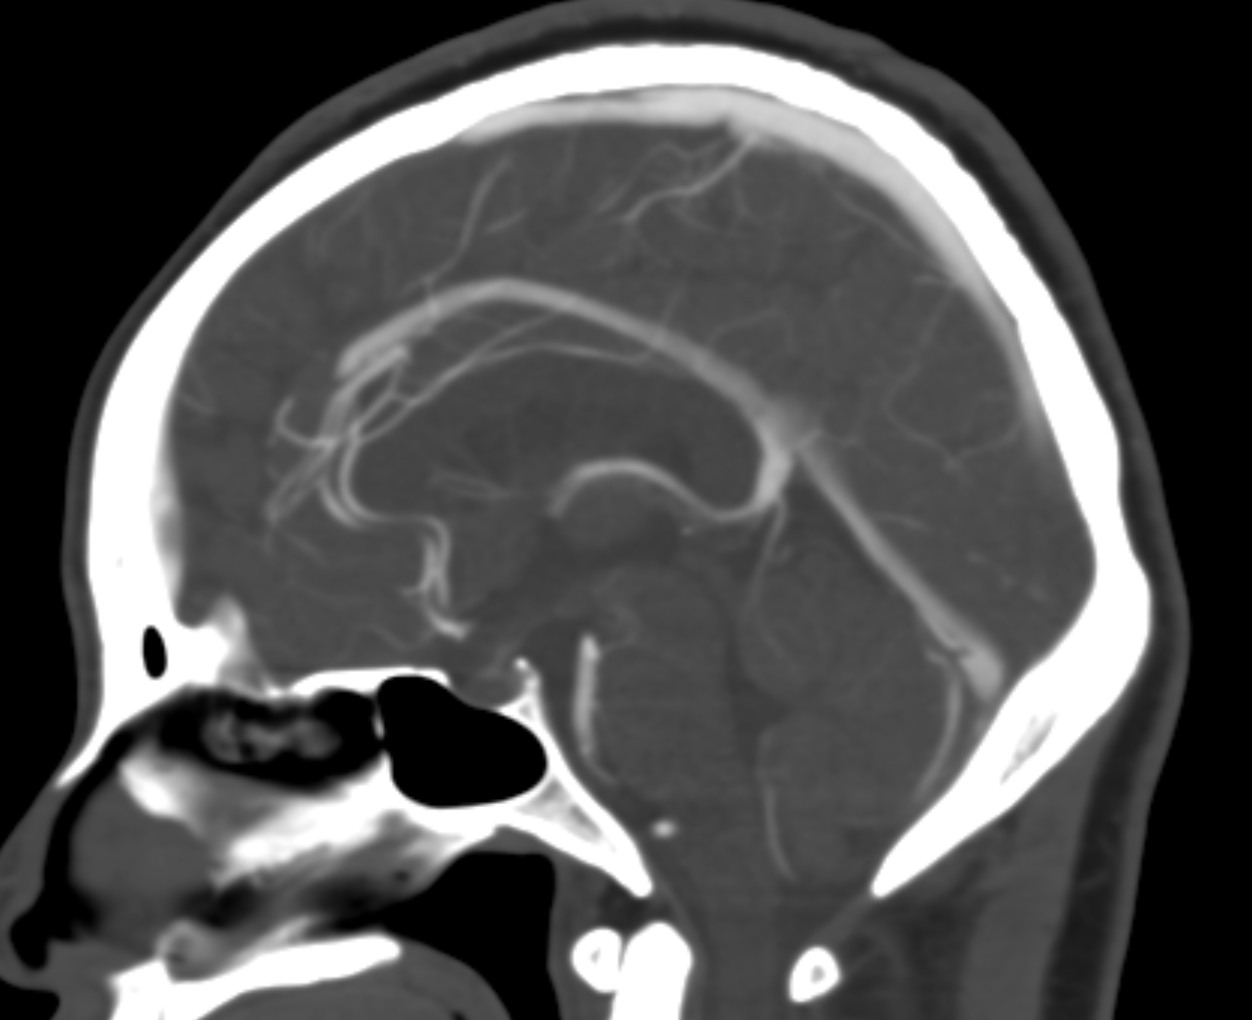

Below are some volumetric images, before we dive in

Pause movies to scroll thru individual frames